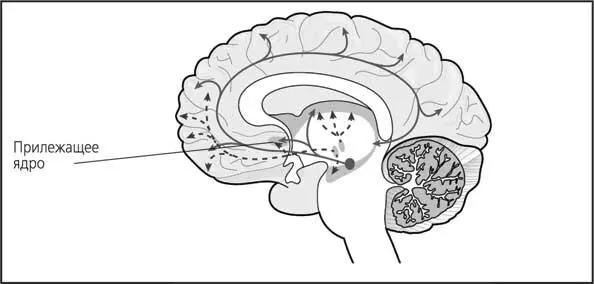

Рис. 24. Объединенная схема путей дофаминовой и серотониновой систем

Оказалось, что схожим образом можно воздействовать и на мозг человека. Многие ученые и журналисты назвали прилежащее ядро «центром удовольствия», но в действительности это не совсем так.

Выяснилось, что прилежащее ядро само по себе не является центром удовольствия: оно способно оценивать ожидаемое удовольствие. Сами Олдс и Милнер писали:

Таким образом, прилежащее ядро (являясь частью дофаминовой системы) участвует в создании состояния ожидания награды. А вот само ощущение удовольствия связано уже с работой гипоталамуса, который обеспечит выброс эндорфинов.